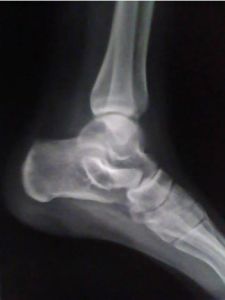

臨床上外側韌帶損傷較為常見,系由足部強力內翻引起。外側韌帶部分撕裂較多見,其臨床表現是踝外側疼痛、腫脹、走路跛行;有時可見皮下瘀血;外側韌帶部位有壓痛;使足內翻時,引起外側韌帶部位疼痛加劇。

踝關節扭傷後,局部軟組織(肌肉、血管及韌帶)因暴力損傷而出血或滲血,使踝部腫脹疼痛,活動後症狀會加重。如果此時按揉或熱敷傷處,不但不能使血腫消退,反而會人為地加重患部的損傷,致使傷處血管擴張,增加出血量,使傷情進一步惡化。有的病人踝關節扭傷後局部傷痛並不是十分明顯,但盲目熱敷處理或草率地揉捏按摩反而會加重踝部傷痛。

關節扭傷後應及時處理,原則是制動和消腫散瘀,使損傷的組織得到良好的修復。關節積血較多者,應在無菌技術下及時抽出,以免後遺關節內粘連。韌帶斷裂或撕脫骨折而影響關節穩定者,需行手術復位修補,以免引起反覆扭傷,關節軟骨損傷和創傷性關節炎。